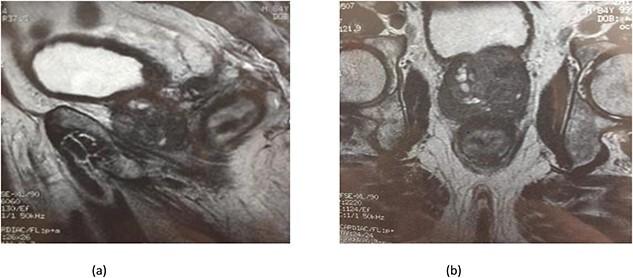

In the pre-prostate specific antigen era, patients with prostate cancer (PC) commonly presented with symptoms. Currently, most PC are diagnosed at an asymptomatic stage with abnormal digital rectal examination or raised prostate specific antigen. In rare cases, PC may infiltrate the rectum and cause symptoms mimicking rectal cancer. It is difficult to differentiate between the two based on clinical features alone. We here report our experience in managing an 86-year-old male, with no significant personal pathological history, who presented with diarrhea and occasional rectal bleeding without any lower urinary tract symptoms. Investigations concluded to a PC invading the rectum and the patient was referred to urology department.

在前列腺特异性抗原出现之前的时代,前列腺癌(PC)患者通常会出现症状。目前,大多数前列腺癌是在无症状阶段通过直肠指检异常或前列腺特异性抗原升高而被诊断出来的。在罕见情况下,前列腺癌可能会浸润直肠并引起类似直肠癌的症状。仅根据临床特征很难区分这两者。我们在此报告我们对一名86岁男性的治疗经验,该患者无重大个人病史,出现腹泻和偶尔的直肠出血,无任何下尿路症状。检查结果显示为前列腺癌侵犯直肠,该患者被转诊至泌尿外科。